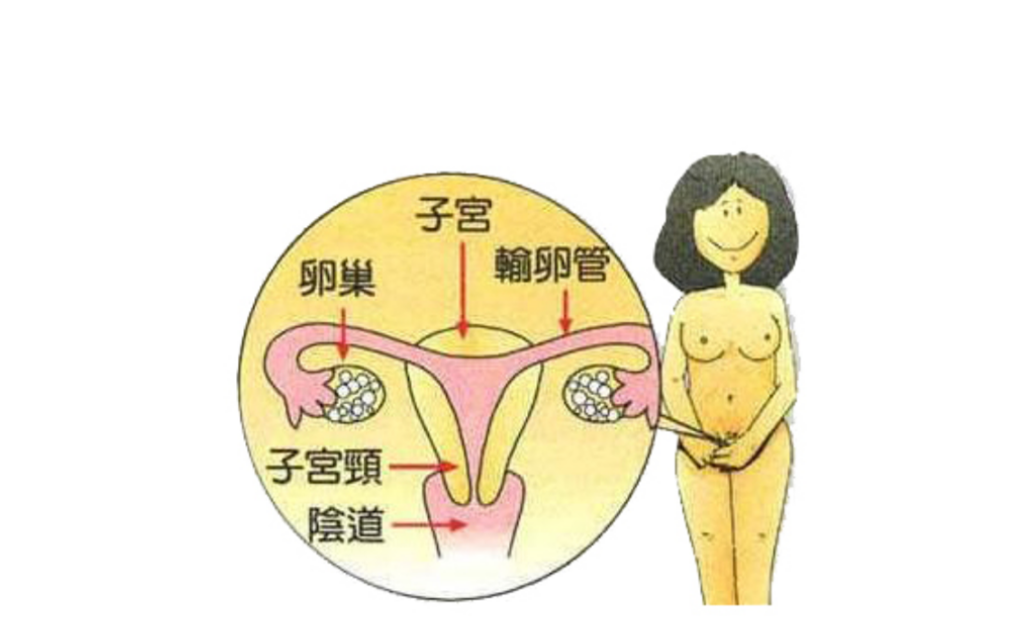

A:陰道癌指的是發生在女性陰道部位的惡性腫瘤,常見的類型有鱗癌和腺癌。如果年輕女性患陰道癌,主要原因可能與人乳頭瘤病毒持續感染有關係。而老年女性,如果盲目使用激素類藥物,陰道黏膜損傷或者是對陰道黏膜持續性的刺激,也可能會造成陰道癌。一些年輕患者……

A:陰道癌就是指陰道內出現有惡性腫瘤。常見的陰道癌包括陰道腺癌、陰道基底細胞癌,以及陰道肉瘤或者疣狀癌等。而陰道癌常常是在陰道的側壁出現菜花樣贅生物,伴有血性的滲出分泌物流出,而且常常會有明顯的疼痛表現。主要的檢查手段就是需要做陰道鏡下的陰道壁……

A:原發的陰道癌其實比較少見,常常是由於宮頸癌或者外陰癌浸潤導致。而陰道癌早期的主要臨床表現,就是會出現陰道不規則出血,而且常常是在同房以後的出血。同時還會出現白帶增多,伴有陰道有水樣,或者血性分泌物,甚至還會伴有惡臭。同時少部分女性還會出現腰……

A:腫瘤原發於陰道的稱為陰道癌症,確診需要組織學病理檢查。主要包括鱗狀細胞癌、腺癌,其他如罕見的惡性黑色素瘤、肉瘤等。主要的臨床表現為絕經後後子宮出血,同房後出血或陰道不規則出血,合併感染時陰道分泌物有臭味。陰道癌的治療以手術治療為主,放療化療……